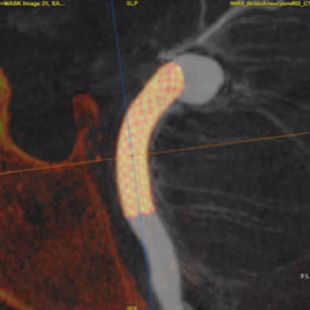

Access

With 3DCT HD and Virtual Dilution visualize the relationship between your device and vessel with robust image quality and without changing your contrast injection protocols. 3,4